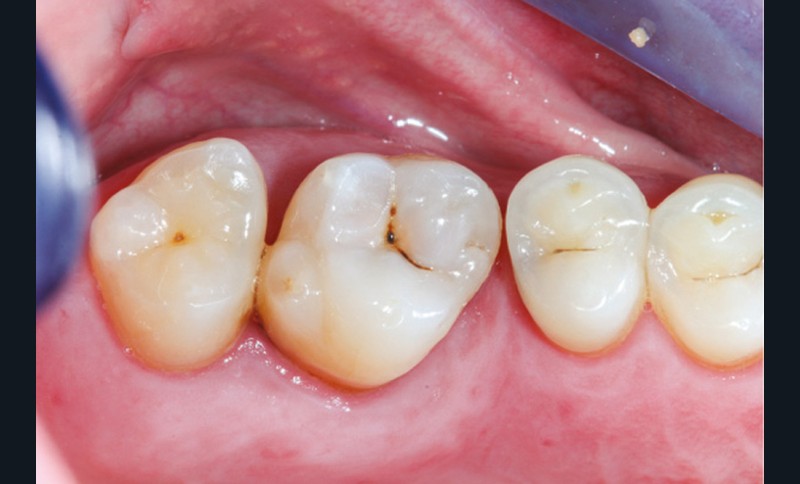

Cette version, quand elle se produit, modifie les espaces interdentaires et complique l’hygiène proximale des patients. Des caries peuvent alors se développer en interproximal sans que cela soit forcément visible à l’examen visuel (fig. 3 et 4). Les radios de type bite-wing (rétro-coronaires) prennent alors tout leur sens (fig. 5 et 6).

La version des dents distales peut aussi avoir des conséquences parodontales désastreuses : sur un parodonte réduit, une hypermobilité peut se développer, une poche parodontale peut aussi apparaître. Chez un patient parodontal, un « effet domino » est possible, des extractions non compensées diminueront donc le pronostic des dents restantes (fig. 7 à 9).